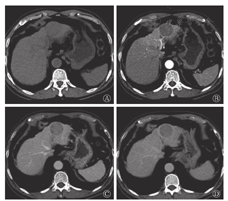

患者男性,69岁,因"常规体检CT发现肝占位6 d"入院,无明显乏力恶心纳差,有乙肝病史。入院后查体:腹部平软,未见腹壁静脉曲张,无压痛及腹肌紧张,未触及腹部包块,肋缘下未触及肝、脾,莫菲氏征阴性。相关实验室检查结果如下,生化:天门冬氨酸氨基转移酶30.3 U/L(正常值为0.0~50.0 U/L),白蛋白40.9 g/L(正常值为36.0~ 55.0 g/L),总胆红素18.6 μmol/L(正常值为2.0~24.0 μmol/L),直接胆红素6.1 μmol/L(正常值为0.0~7.5 μmol/L),间接胆红素11.0 μmol/L(正常值为1.7~17.0 μmol/L);肿瘤标志物:甲胎蛋白16.0 μg/L(正常值为0~20.0 μg/L),癌胚抗原2.9 μg/L(正常值为0.0~5.0 μg/L)。CT肝脏三期增强扫描显示(图1):肝左外叶上段低密度结节灶,大小约36mm× 39 mm,无明显强化,边界基本清晰,性质难定,鉴于患者有乙肝病史,肝癌待排除。为进一步诊治行PET/CT检查。

Dynamic contrast-enhanced CT imagings pf liver(male,69 years old )